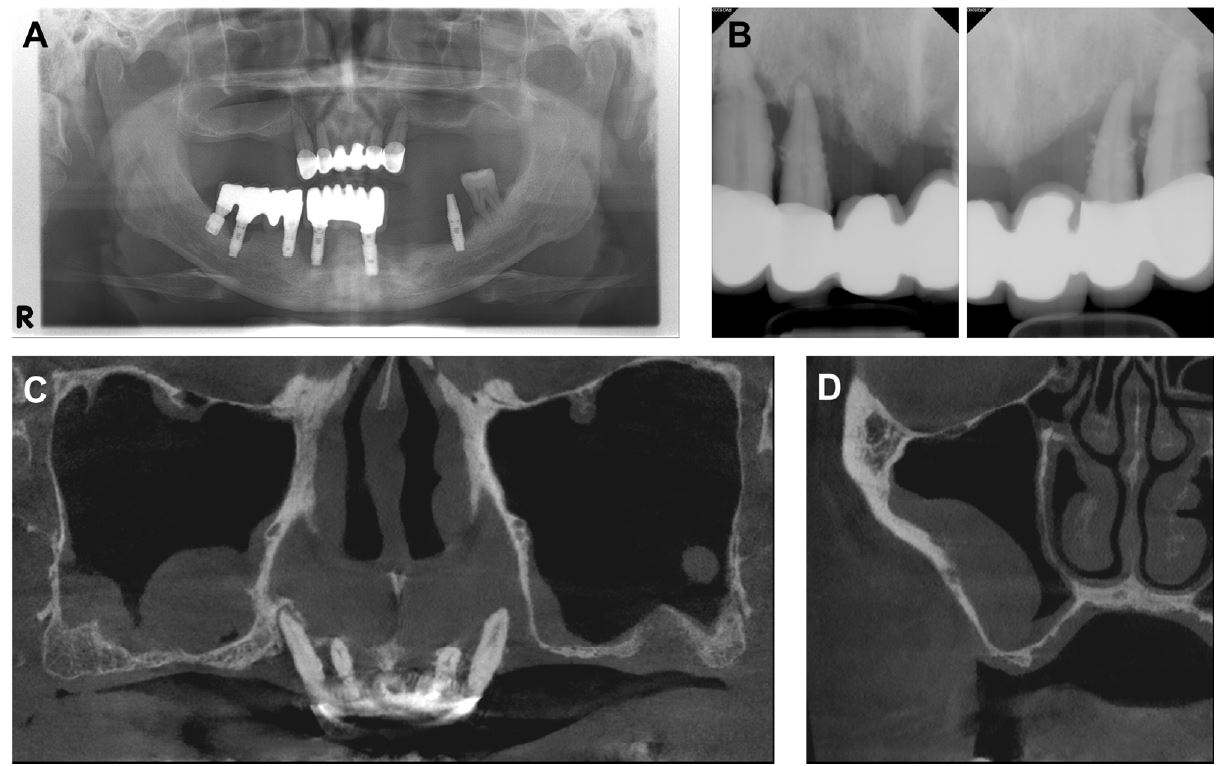

A 47-year-old male patient visited our hospital with a discomfort due to mobility of the remaining teeth and reduced masticatory function. The patient had been using a removable partial denture with a six-unit fixed prosthesis from the upper right canine to the upper left canine. Panoramic view revealed severe vertical resorption of both posterior alveolar bone (Fig. 1A) and remaining hopeless teeth with chronic periodontitis (Fig. 1B). The patient’s condition required overall restoration after extraction of all remaining maxillary dentition. The patient also showed peri-implant disease and vertical bone resorption in the lower jaw with inappropriately placed implants.

Fig. 1.

Radiographic image on first visit. (A) Panoramic view presenting alveolar bone resorption and pneumatization of both sinus floors, (B) Intraoral radiography showing the remaining tooth with chronic periodontitis, (C and D) Cone-beam computed tomography CBCT of the maxillary sinus revealing mucosal thickening, particularly in the right sinus floor.

The cone-beam computed tomography (CBCT) scan revealed severe bone loss in both the anterior and posterior areas of the maxillary alveolar bone (Fig. 1C). In addition, we observed considerable mucosal thickening of the right maxillary sinus floor extending more than one-third of sinus height (Fig. 1D). When informed about the radiographic signs, the patient reported medical history pertaining to respiratory problems and nasal symptoms, which had been persistent for more than several months prior to the visit. We then referred the patient to an otolaryngologist for examination and treatment of the maxillary sinus before starting dental treatment. The patient was diagnosed with chronic rhinosinusitis by the otolaryngologist and was advised to undergo dental surgery after several weeks of medication.